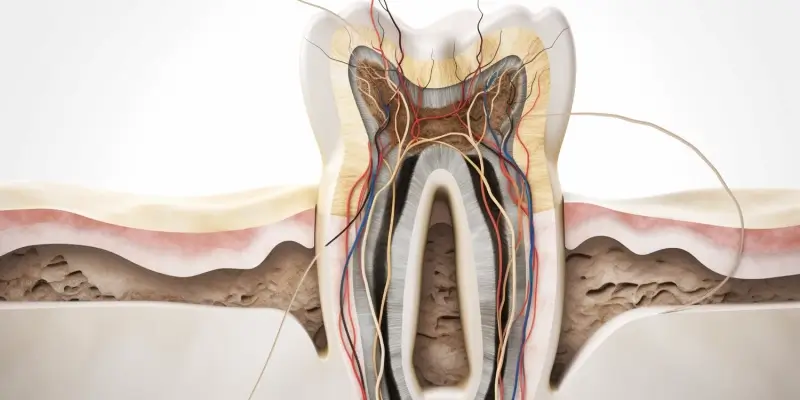

Przyczyny zapalenia okostnej zęba mogą być różnorodne i często związane są z infekcjami bakteryjnymi. Najczęściej schorzenie to rozwija się w wyniku nieleczonej próchnicy, która prowadzi do zakażenia miazgi zęba. Gdy bakterie dostaną się do wnętrza zęba, mogą rozprzestrzenić się na otaczające tkanki, w tym okostną. Inną częstą przyczyną jest uraz mechaniczny, który może spowodować uszkodzenie tkanek i sprzyjać rozwojowi stanu zapalnego. Często zapalenie okostnej występuje również po zabiegach stomatologicznych, takich jak ekstrakcja zęba lub leczenie kanałowe, gdy bakterie mają możliwość przedostania się do głębszych warstw tkanek. Osoby z osłabionym układem odpornościowym są bardziej narażone na rozwój tego schorzenia, ponieważ ich organizm ma trudności w zwalczaniu infekcji.

Jakie są metody diagnostyczne zapalenia okostnej zęba

Diagnostyka zapalenia okostnej zęba opiera się na kilku kluczowych metodach, które pozwalają lekarzowi na postawienie trafnej diagnozy. Pierwszym krokiem jest dokładny wywiad lekarski, w którym pacjent opisuje swoje objawy oraz historię medyczną. Lekarz zwraca uwagę na lokalizację bólu, jego nasilenie oraz czas trwania. Następnie przeprowadza badanie kliniczne jamy ustnej, podczas którego ocenia stan zębów oraz tkanek otaczających. W przypadku podejrzenia zapalenia okostnej istotne jest także wykonanie zdjęcia rentgenowskiego, które pozwala zobaczyć zmiany w strukturze kości oraz obecność ewentualnych ropni czy innych patologii. W niektórych przypadkach lekarz może zalecić dodatkowe badania laboratoryjne, takie jak morfologia krwi czy posiew bakteriologiczny, aby określić rodzaj bakterii odpowiedzialnych za infekcję.